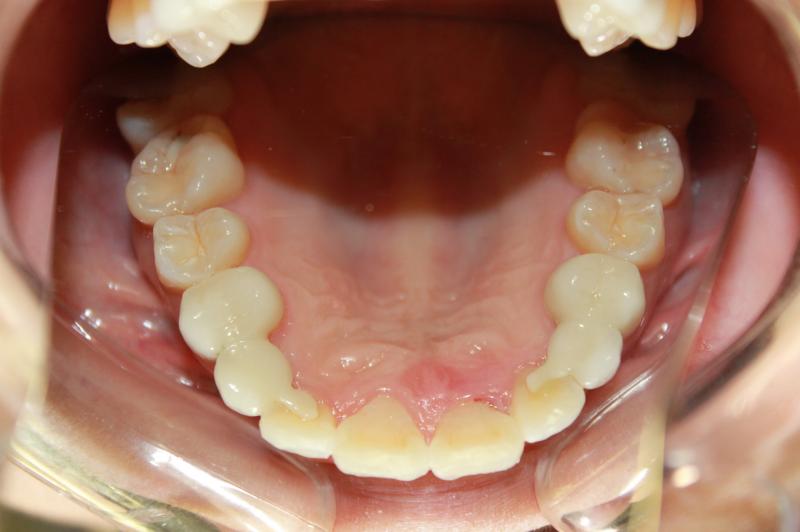

INVISALIGN - 13 months, 1 lower tooth removal, 1 series of aligners to align teeth and create the proper amount of space for 2 cantilever bridge to replace congenitally missing cuspids. COSMETIC DENTISTRY - 2 porcelain cantilever bridges and cosmetic bonding to reshape incisors and close gingival spaces. TOTAL TREATMENT TIME, 15 months

Cosmetic Dentistry, Mid-line Asymetry, Missing Teeth, Severe Crowding